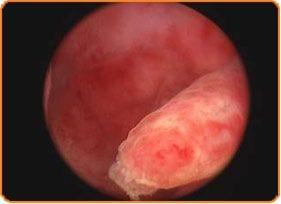

- prezența polipilor sau a fibroamelor

- extirparea polipilor